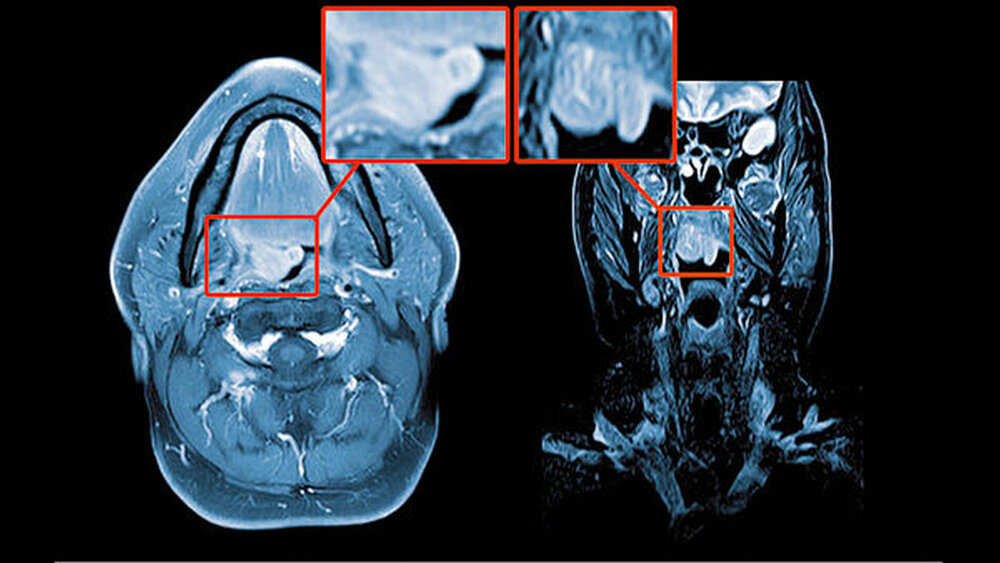

Die endoskopische Untersuchung wie auch die MRT-Untersuchung (Abbildung 1) bestätigten den Verdacht auf eine benigne, im Bereich des weichen Gaumens rechts lokalisierte Neoplasie.

Die präoperative, nicht invasive Diagnostik ist schwierig und nur mittels Magnetresonanztomogramm sinnvoll möglich. Hier zeigen die Tumore eine geringe Hyperintensität und Isointensität in der T1- und in der T2-Wichtung bei insgesamt homogener Signalintensität der glatt begrenzten Raumforderung ohne Infiltration des umgebenden Gewebes. Als Methode zur Diagnosesicherung vor Therapie kommt die Feinnadel- oder die Skalpellbiopsie infrage [Bertholf et al., 1988; McGregor et al., 2003].